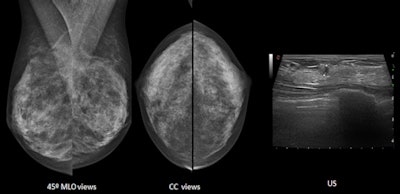

First up, Dr. Fiona Gilbert from the department of radiology at the University of Cambridge in the U.K. will address the "problem child" modality radiologists must deal with on a regular basis: mammography. ECR delegates will learn about the definition of dense breasts and what they look like on mammography. In addition, they will understand the different methods to measure breast density on mammography and analyze details that can be associated with abnormalities in dense tissues.

Breast density can be measured using different techniques such as the Boyd and Cumulus techniques, and there are different scoring systems for assessing the amount of breast density on mammography, particularly the BI-RADS systems, and the Royal College of Radiologists (RCR) breast group system. In addition, quantitative methods are becoming available, such as Volpara and Quantra software.

"The reason these techniques are important is because firstly, and most importantly, an assessment of breast density on mammography gives the reader an indication of sensitivity of the mammogram to detecting breast cancer. BI-RADS 4, BI-RADS D, or 'dense breast' in the U.K., implies that the sensitivity is reduced compared with someone who has fatty breasts or BI-RADS A or I," she said. "There is a masking effect because of dense breast tissue, reducing the likelihood of detecting breast cancer."

Dr. Luis Pina Insausti from the department of radiology at Clinica Universitaria de Navarra in Pamplona, Spain, will discuss ultrasound and dense breasts. Ultrasound can detect additional breast cancers in dense breasts after negative mammography, increasing the detection rate of breast cancer by up to 37%.

The American College of Radiology BI-RADS lexicon describes three patterns for ultrasound breast composition: homogeneous echotexture -- fat, homogeneous echotexture -- fibroglandular, and heterogeneous echotexture. The patterns have similarities with mammographic density patterns (dense mammographic patterns can be seen as homogenous echotexture -- fibroglandular and heterogeneous echotexture patterns).

"Due to the fact that most benign and malignant lesions are usually seen as hypoechoic masses, these lesions are better detected on homogeneous echotexture -- fibroglandular than on the other patterns," he added.

Moreover, there are other less obvious factors that can influence the detection of lesions with ultrasound: volume of the breast (attenuation of ultrasound in large-sized breasts can decrease the sensitivity of ultrasound), localization of the lesion (worse visualization in deeply or superficially located lesions, or lesions located behind the nipple or scars), and atypical appearance of some breast cancers (hyper- or isoechoic cancers, subtle distortions, etc.).